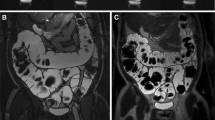

After 20 min of retention enema with Gd-FITC-SLNs, dynamic MRI showed colorectal wall enhancement due to nano-contrast agent absorption. The degree of enhancement presented the following pattern: acute UC > normal intestinal wall > chronic UC (Figs. 2 and 3). The colorectal wall in the acute UC group was continuously enhanced for 120 min, the normal intestinal wall showed rapid metabolization of the contrast agent, and the degree of enhancement decreased with time, while in the chronic UC group, the colorectal wall only showed slight enhancement. After 20 min of enema with Gd-FITC-SLNs, the rectal wall enhancement of mice with acute UC was similar to those administered with intravenous Gd-DTPA, but the enhancement time was longer with enema than with intravenous injection (Figs. 4 and 5). In addition, intravenous Gd-FITC-SLN injection conferred a better contrast effect.

MR images of acute UC, chronic UC, and normal mice in the colorectum of mice. Dynamic MR imaging showed that the intestinal wall of acute inflammation was significantly enhanced after 20 min of retention enema with nano-contrast agent Gd-FITC-SLNs. The degree of enhancement was as follows: acute UC > normal intestinal wall > chronic UC